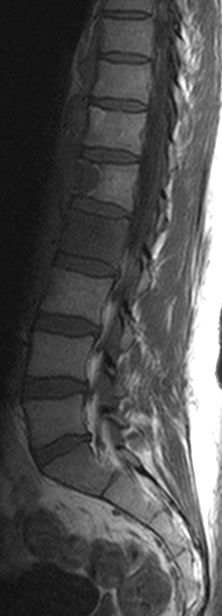

Rezidiv 1 Jahr nach follikulärem Lymphom

MRT